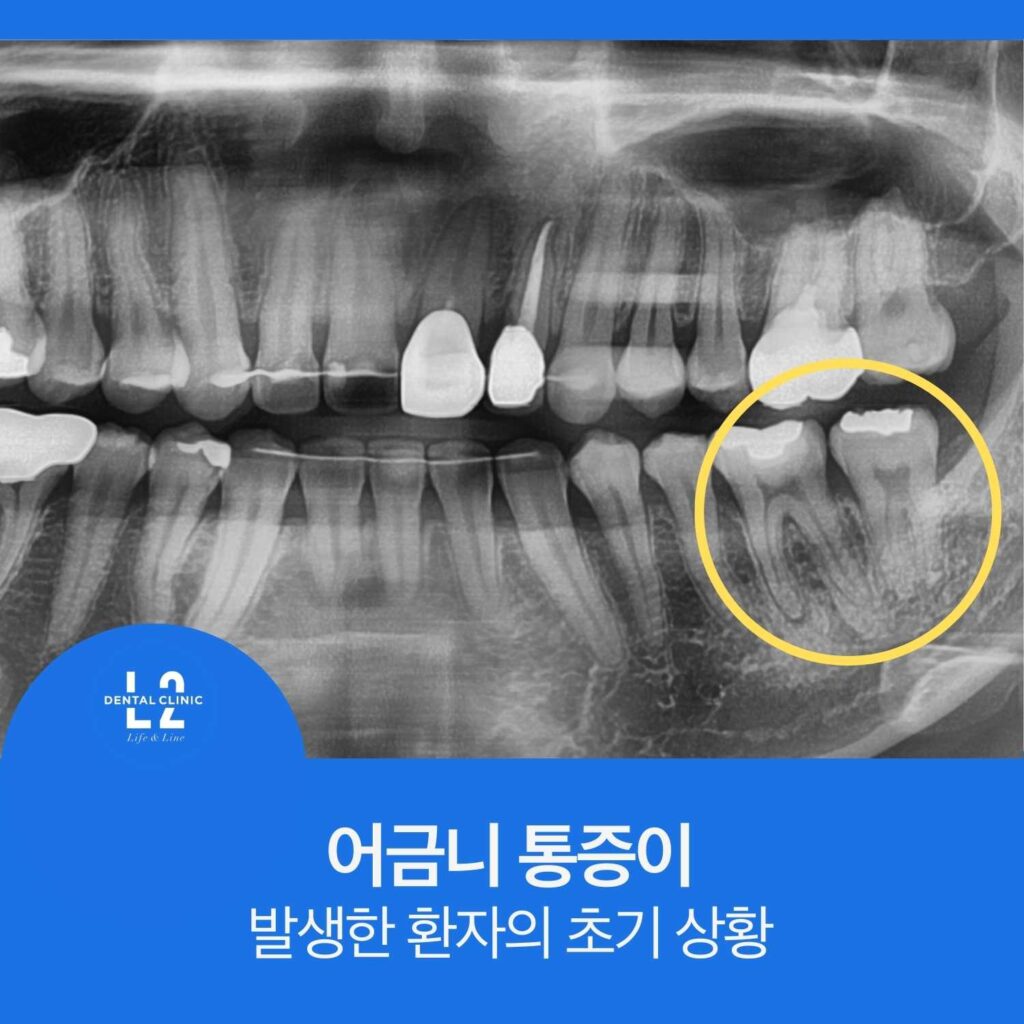

1. 어금니 통증이 발생한 환자의 초기 상황

정기검진을 꾸준히 받아오던 환자분이었습니다.

1년 전 검진에서 왼쪽 아래 어금니의 골드 인레이 주변이 다소 어둡게 보이는 소견이 있었지만,

당시에는 다음과 같은 이유로 치료를 바로 진행하지 않았습니다.

- 환자에게 증상이 없었고

- 큐레이 형광 검사에서도 명확한 이차충치 소견이 확인되지 않았으며

- 치료를 진행할 경우 신경치료까지 이어질 가능성이 높았기 때문입니다.

따라서 그 당시에는 보존적인 판단으로 경과관찰을 하기로 했습니다.

촬영한 엑스레이에서는

이전과 비교했을 때 치아 뿌리 끝 부위가 더 어두워진 모습이 확인되었습니다.

이러한 변화는 일반적으로

- 치수염 진행

- 치수 괴사

- 치근단 염증

과 같은 문제를 의심하게 만드는 소견입니다.

즉, 이전에 의심했던 골드인레이 하방 문제가 실제로 진행된 것으로 판단할 수 있었습니다.